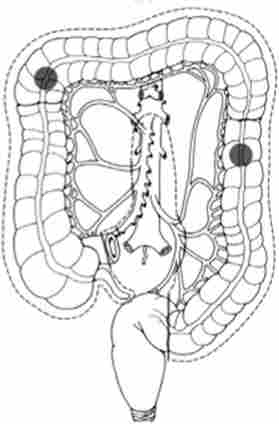

Найбільш часто рак розвивається в сигмовидної і сліпій кишці. Детально частота ураження різних відділів ободової кишки представлена на рис. 14.4.

Частота ураження карциномою різних відділів ободової кишки

Мал. 14.4. Частота ураження карциномою різних відділів ободової кишки